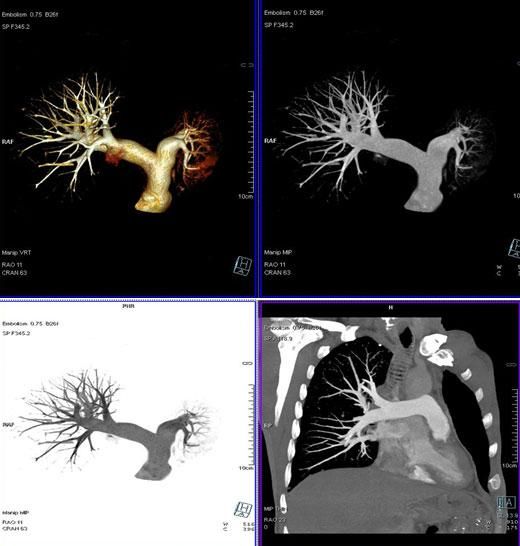

3、肺動脈血管成像: